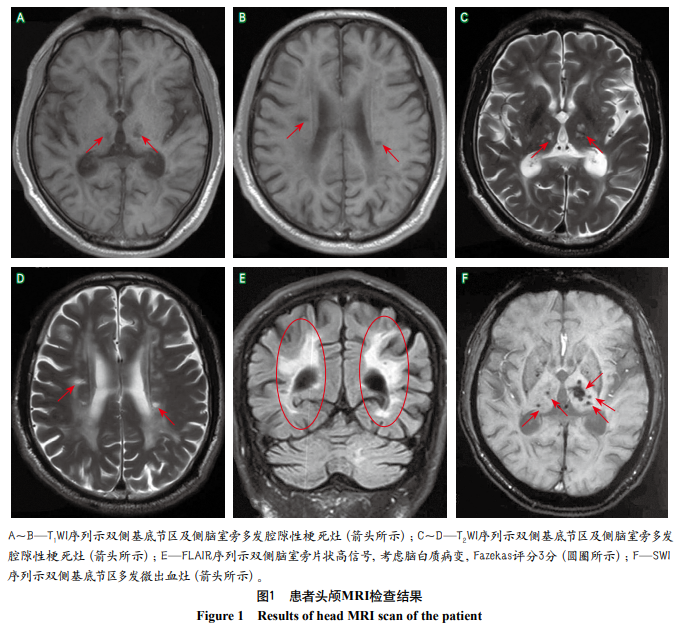

影像学检查:头颅MRI检查(2019-08-08)示双侧小脑、双侧基底节区、丘脑、半卵圆区及双侧额叶皮质下多发腔隙性梗死灶(图1A~D),脑白质变性(Fazekas评分3分)(图1E)。头颅SWI(2019-08-09)示双侧基底节区、丘脑、半卵圆区及右侧小脑多发微出血灶(图1F)。